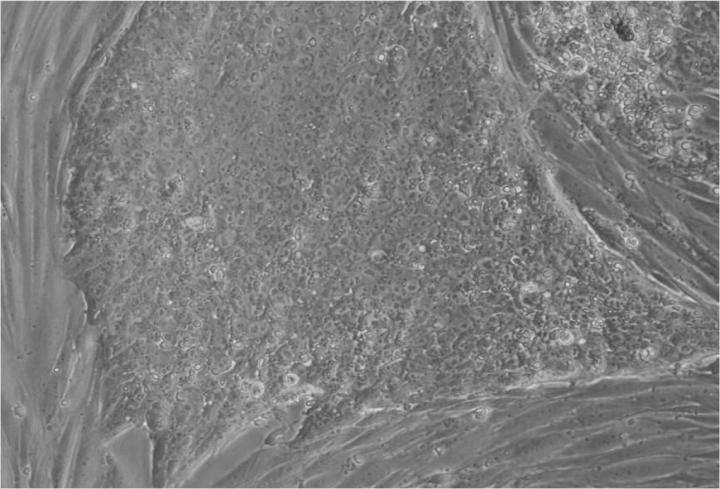

人類胚胎干細胞 (ESC) 是從囊胚(一種非常早期的人類胚胎)中發現的少量細胞產生的。從囊胚中取出的單個細胞生長成大量細胞以產生 ESC“系”。

Jenny Nichols 拍攝的人類囊胚和人類胚胎干細胞圖像。愛丁堡大學 MRC 再生醫學中心向 SCNT 和多莉羊注射細胞核。